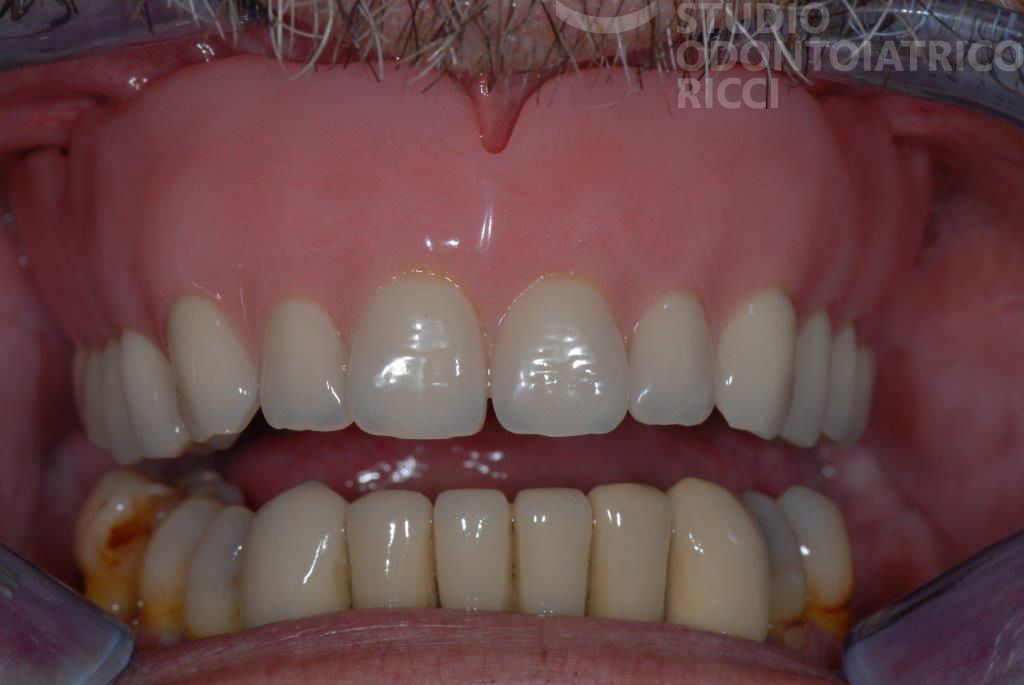

È la soluzione ideale per sostituire un singolo dente mancante. L’impianto viene inserito nello spazio lasciato dal dente perso, senza limare i denti vicini. Garantisce un risultato funzionale, estetico e biologicamente conservativo.

In determinati casi selezionati, è possibile applicare la protesi provvisoria lo stesso giorno dell’intervento implantare. Questa tecnica, chiamata carico immediato, viene spesso impiegata:

In aree con elevata valenza estetica (zona frontale)

Il vantaggio principale è la rapidità del risultato estetico e funzionale, mantenendo comfort e sicurezza.